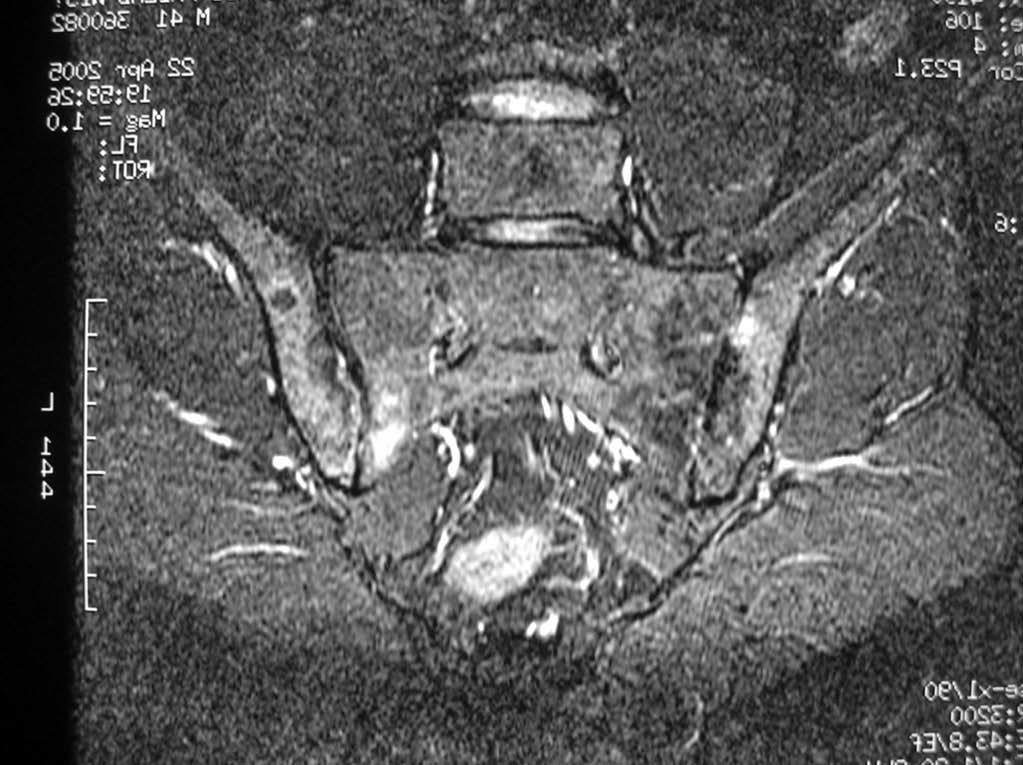

La afectación inflamatoria se manifestó, en todos los casos, como hiperintensidad en secuencia STIR y captación de contraste en secuencias T1. Doce pacientes presentaron afectación inflamatoria en la columna, ASI o caderas (figs. 1, 2 y 3).

Fig. 2.--Afectación inflamatoria sacroilíaca. Secuencia STIR.